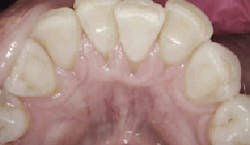

Taken after probing on July 7, 2016. Image courtesy of Perfect Teeth–Frank Lloyd Wright.